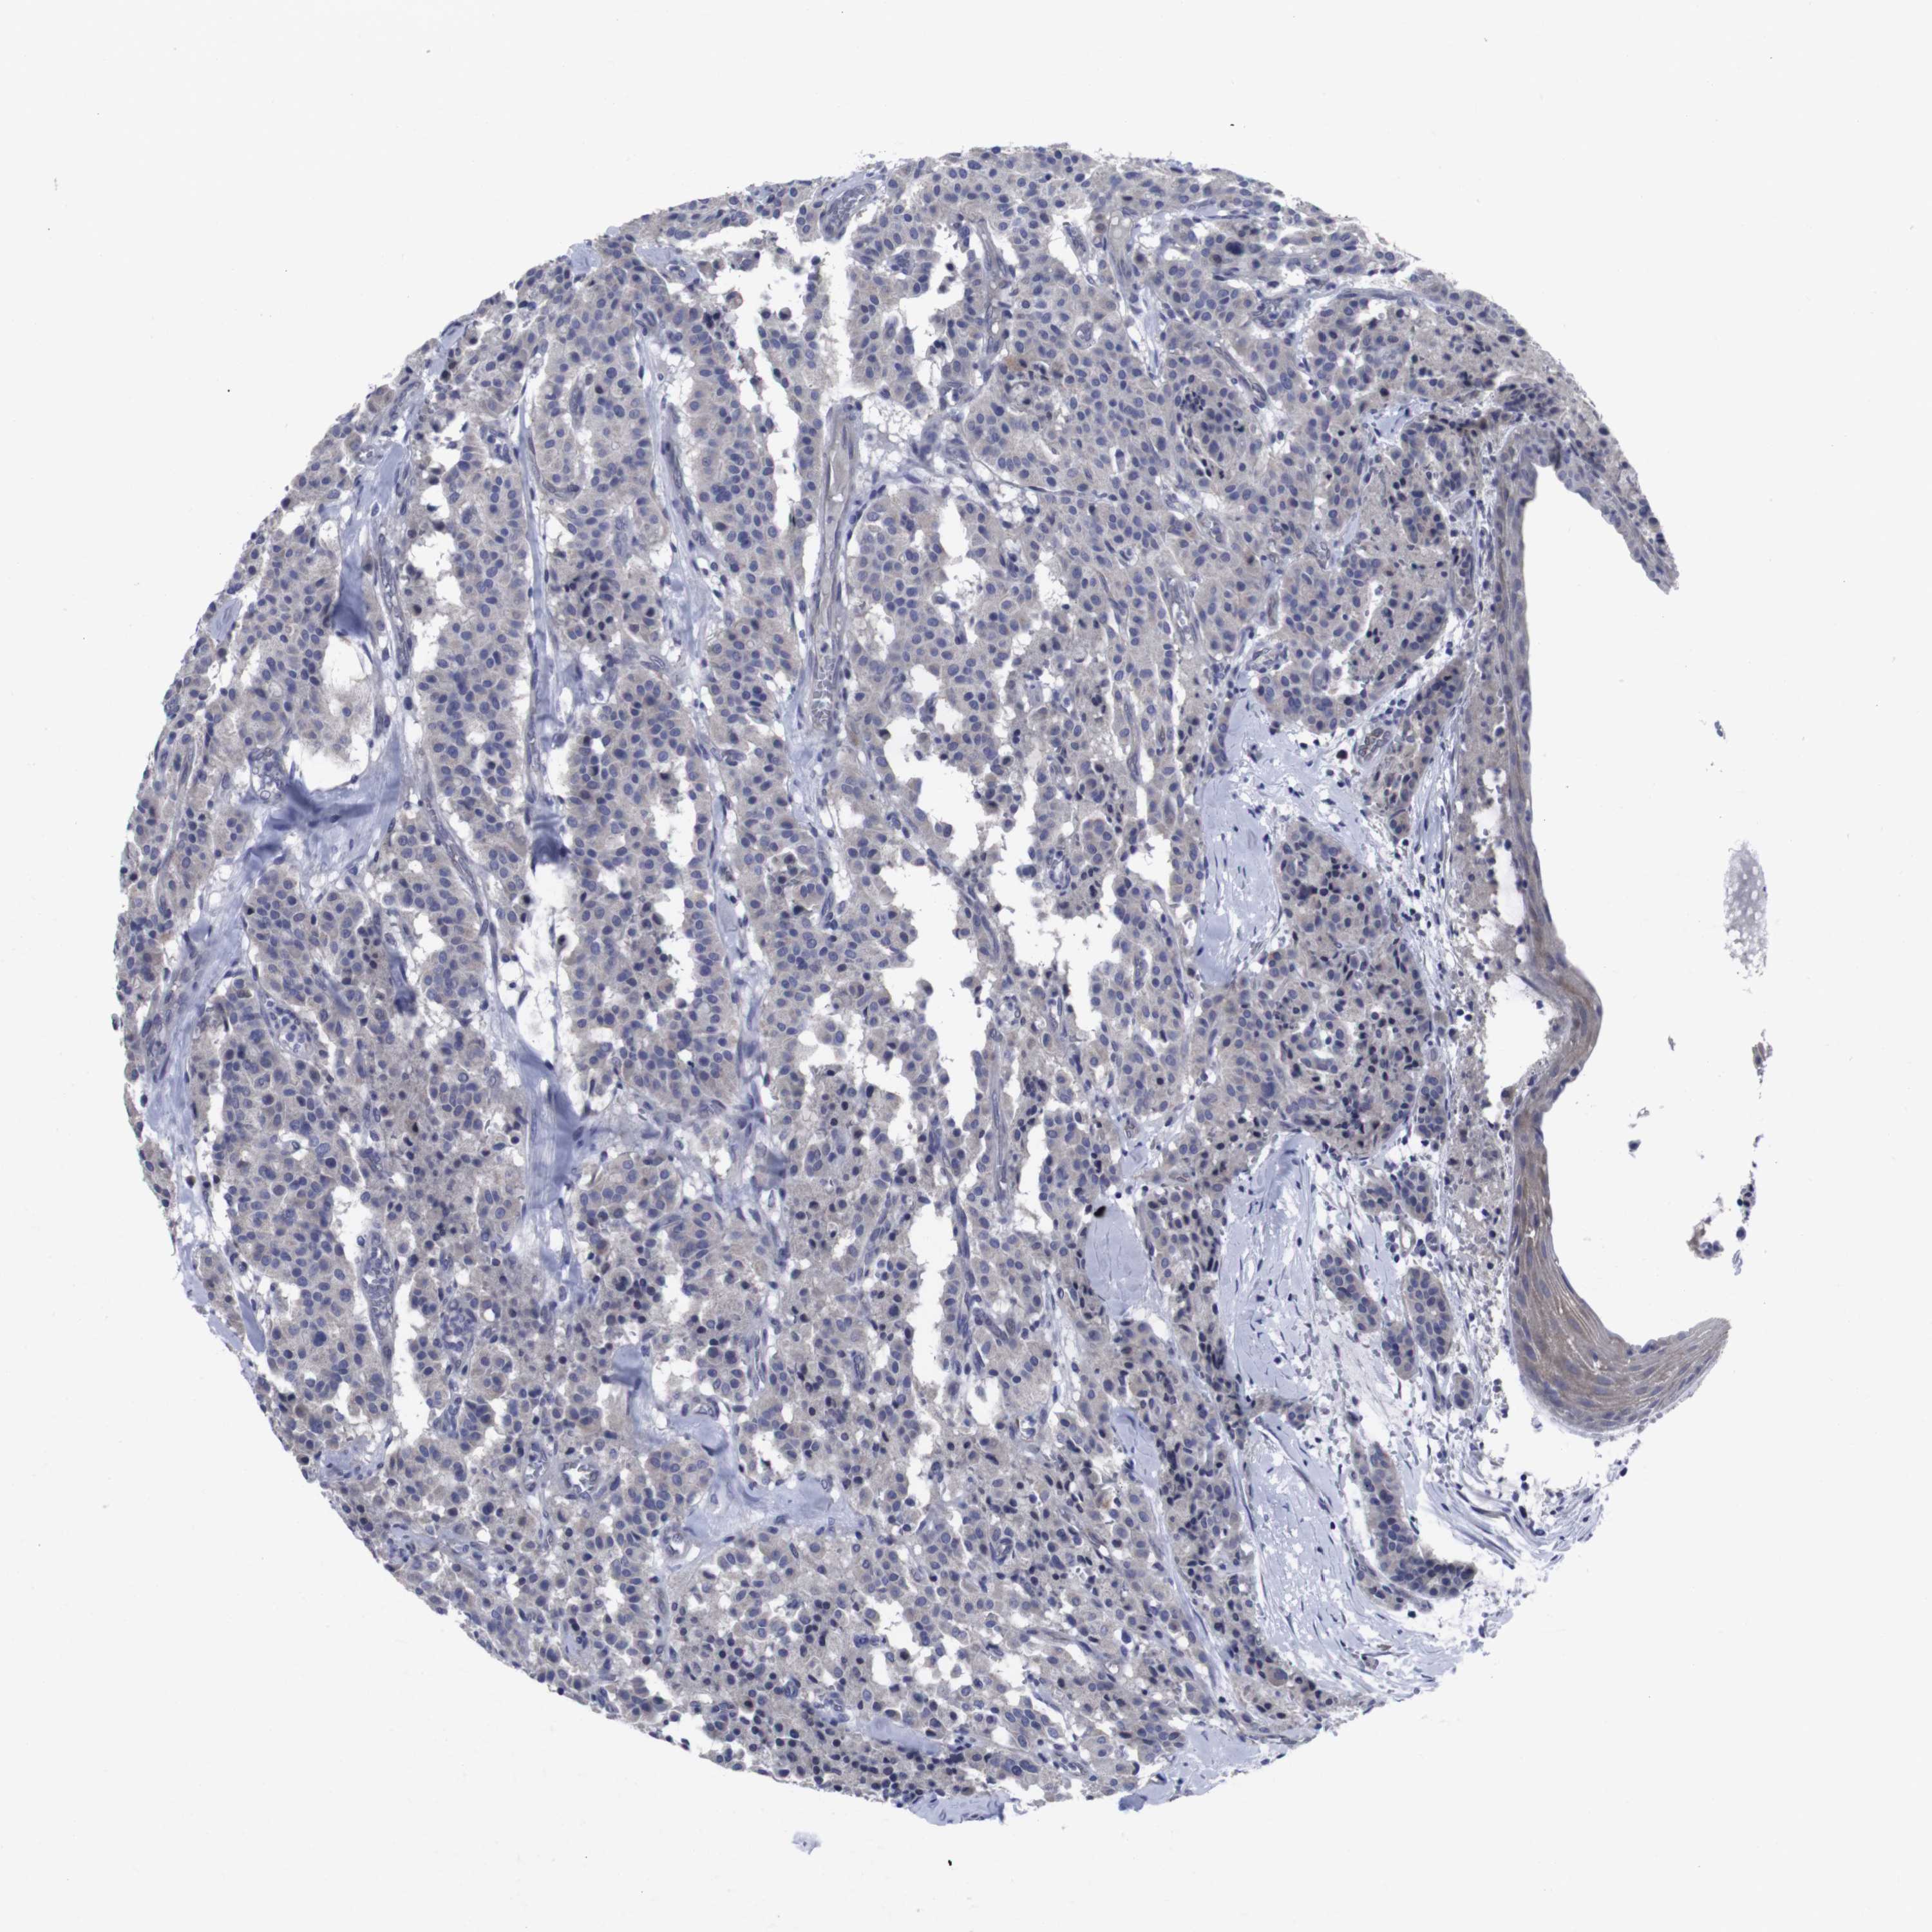

CARCINOID - Protein expressioni

A mouse-over function shows sample information and annotation data. Click on an image to view it in a full screen mode. Samples can be filtered based on level of antibody staining by selecting one or several of the following categories: high, medium, low and not detected. The assay and annotation is described here.

Antibody stainingi

Antibody staining in the annotated cell types in the current human tissue is reported as not detected, low, medium, or high, based on conventional immunohistochemistry profiling in selected tissues. This score is based on the combination of the staining intensity and fraction of stained cells.

Each image is clickable and will lead to virtual microscopy that enables deeper exploration of all samples and also displays staining intensity scores, fraction scores and subcellular localization as well as patient and tissue information for each sample.

Antibody CAB001452

Staining

High

Medium

Low

Not detected

Intensity

Strong

Moderate

Weak

Negative

Quantity

>75%

75%-25%

<25%

None

Location

Nuclear

Cytoplasmic/membranous

Cytoplasmic/membranous,nuclear

Carcinoid, malignant, NOS

Carcinoma, NOS